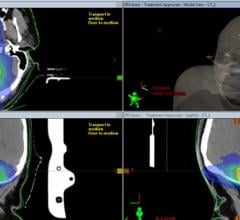

The radiation therapy channel covers all aspects of radiation oncology technology. Radiation therapy includes linear accelerators (LINAC), proton therapy, brachytherapy, image guided radiation therapy (IGRT), focused ultrasound, stereotactic body radiation therapy (SBRT), intensity modulated radiation therapy (IMRT), treatment planning systems and tomotherapy.

Automation is transforming the way we practice radiation oncology and advancing the standard of patient care. There have ...

Sept. 25, 2025 — GE HealthCare has announced updates to Intelligent Radiation Therapy (iRT), a new version of the ...